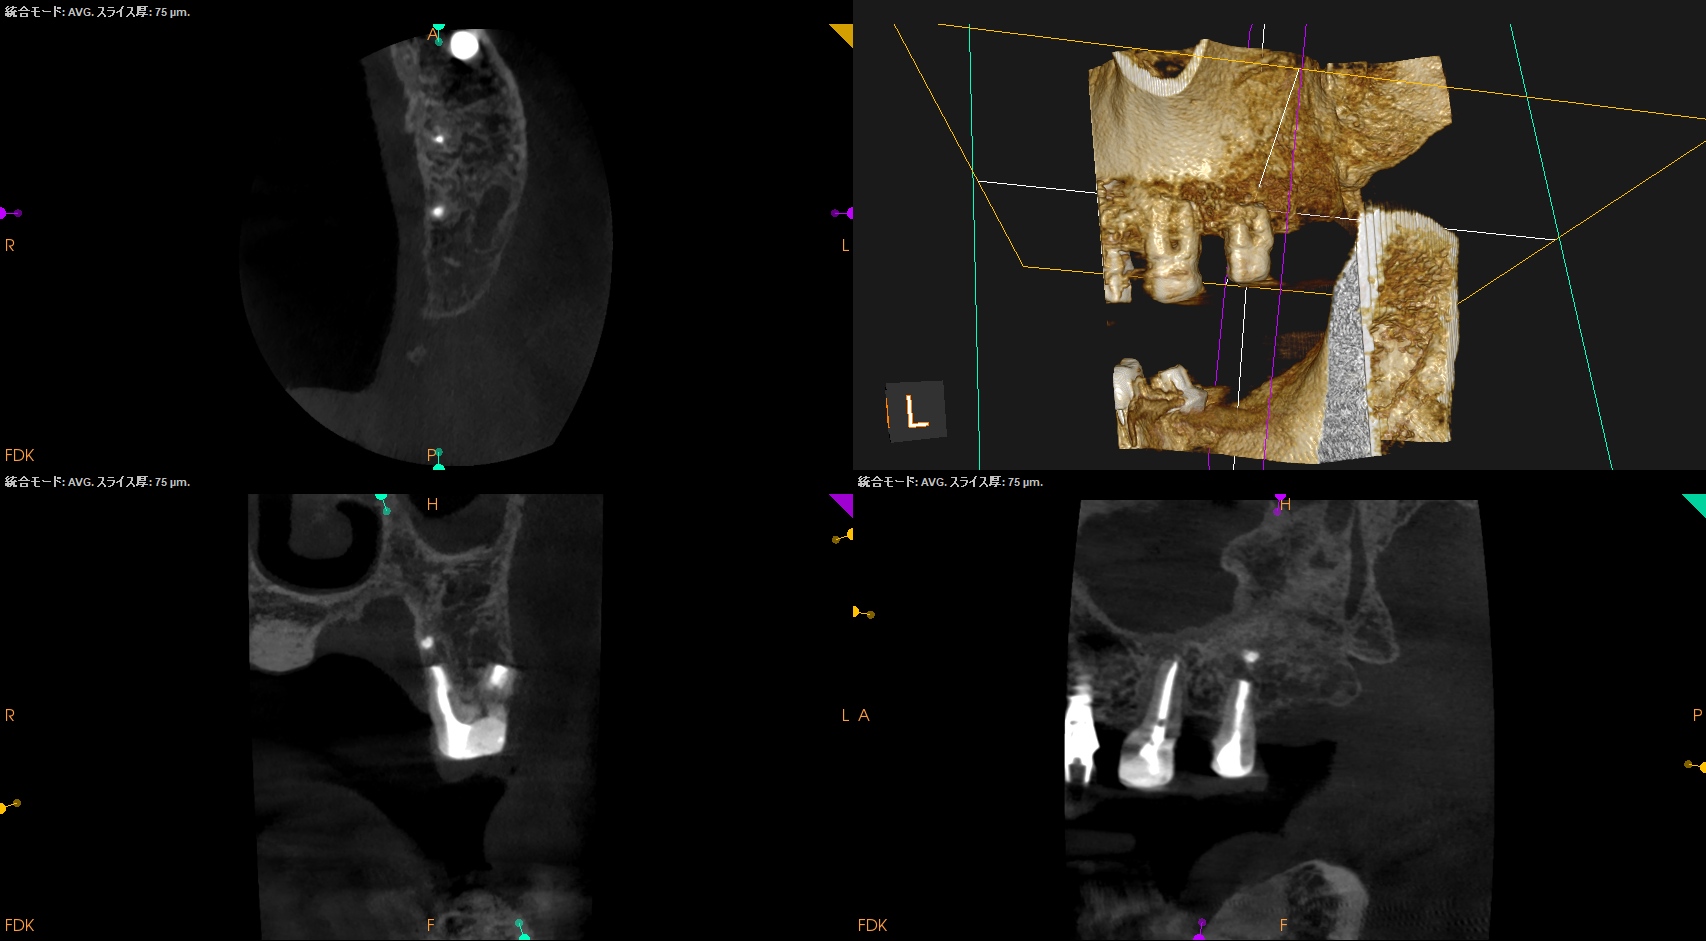

#15 Intentional Replantation 6M recall(2025.10.8)

術前の臨床症状は喪失した。

術直後と比較した。

歯槽骨がだいぶ回復している。